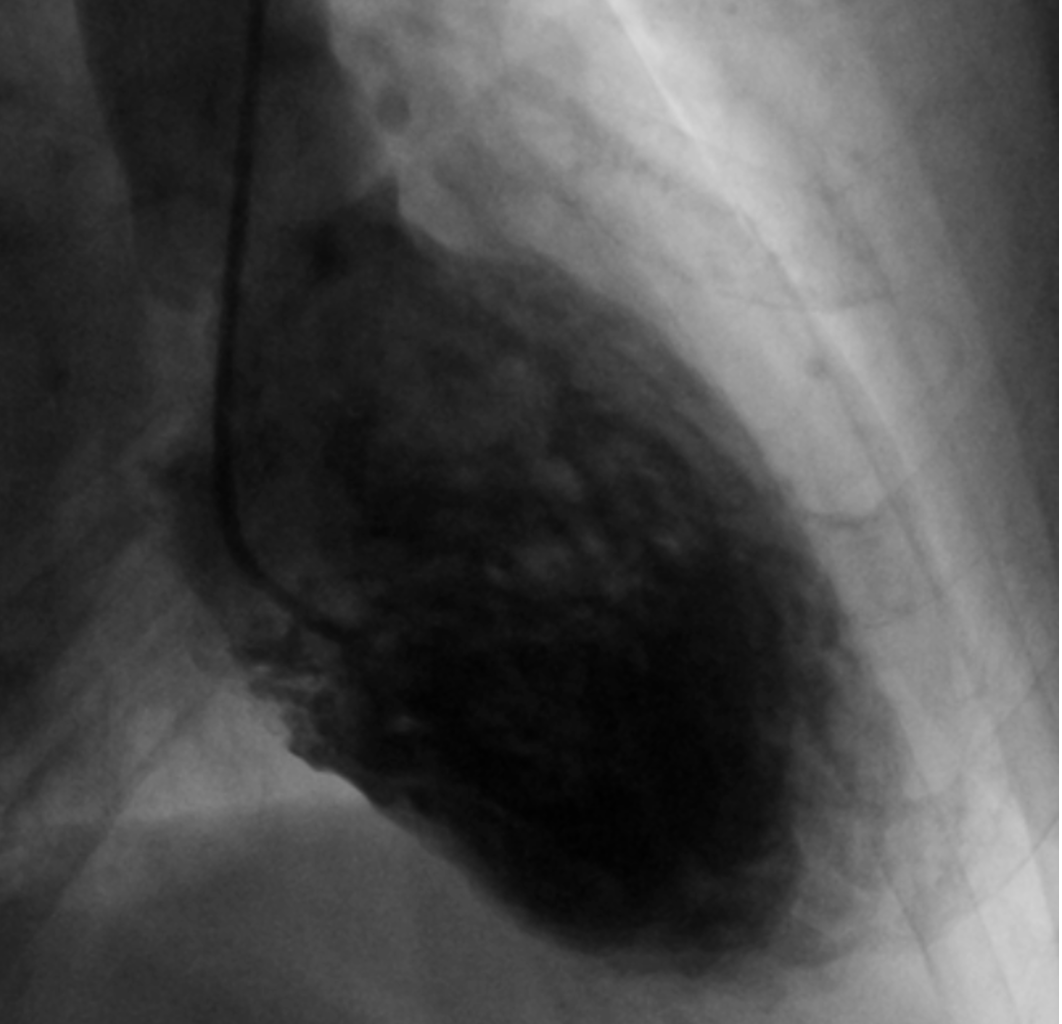

LVgram in systole: